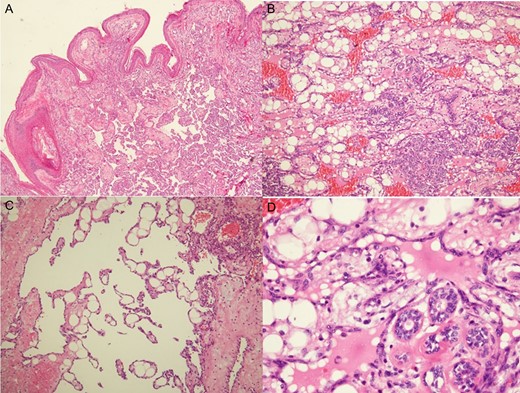

Histologic examination revealed low-grade angiosarcomas on sections of the skin nodules (A) and a mammary mass with lesions varying from well to poorly differentiated vascular neoplasms. The well-differentiated component comprised distinct anastomosing vascular channels that dissected the adipose tissue and lobular stroma (B). Neoplastic vessels had variably dilated or angulated lumina (C). The nuclei of the endothelial lining of the neoplastic vessels was prominent and hyperchromatic, but mitotic activity was infrequent, and there was typically no endothelial multilayering (D).